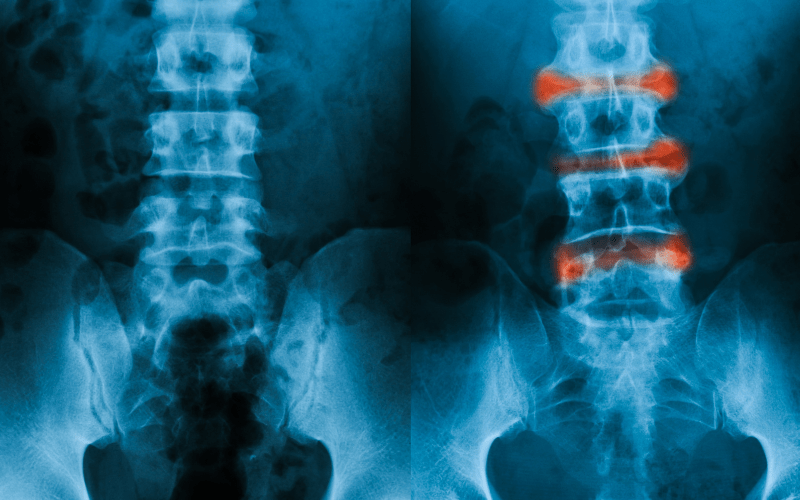

Nos ocupamos del diagnóstico y tratamiento de afecciones musculoesqueléticas, autoinmunes e inflamatorias, en personas de todas las edades.

Si usted siente dolor en los huesos, músculos, ligamentos, articulaciones y tendones, no dude en asistir a un reumatólogo.

Espondilitis anquilosante